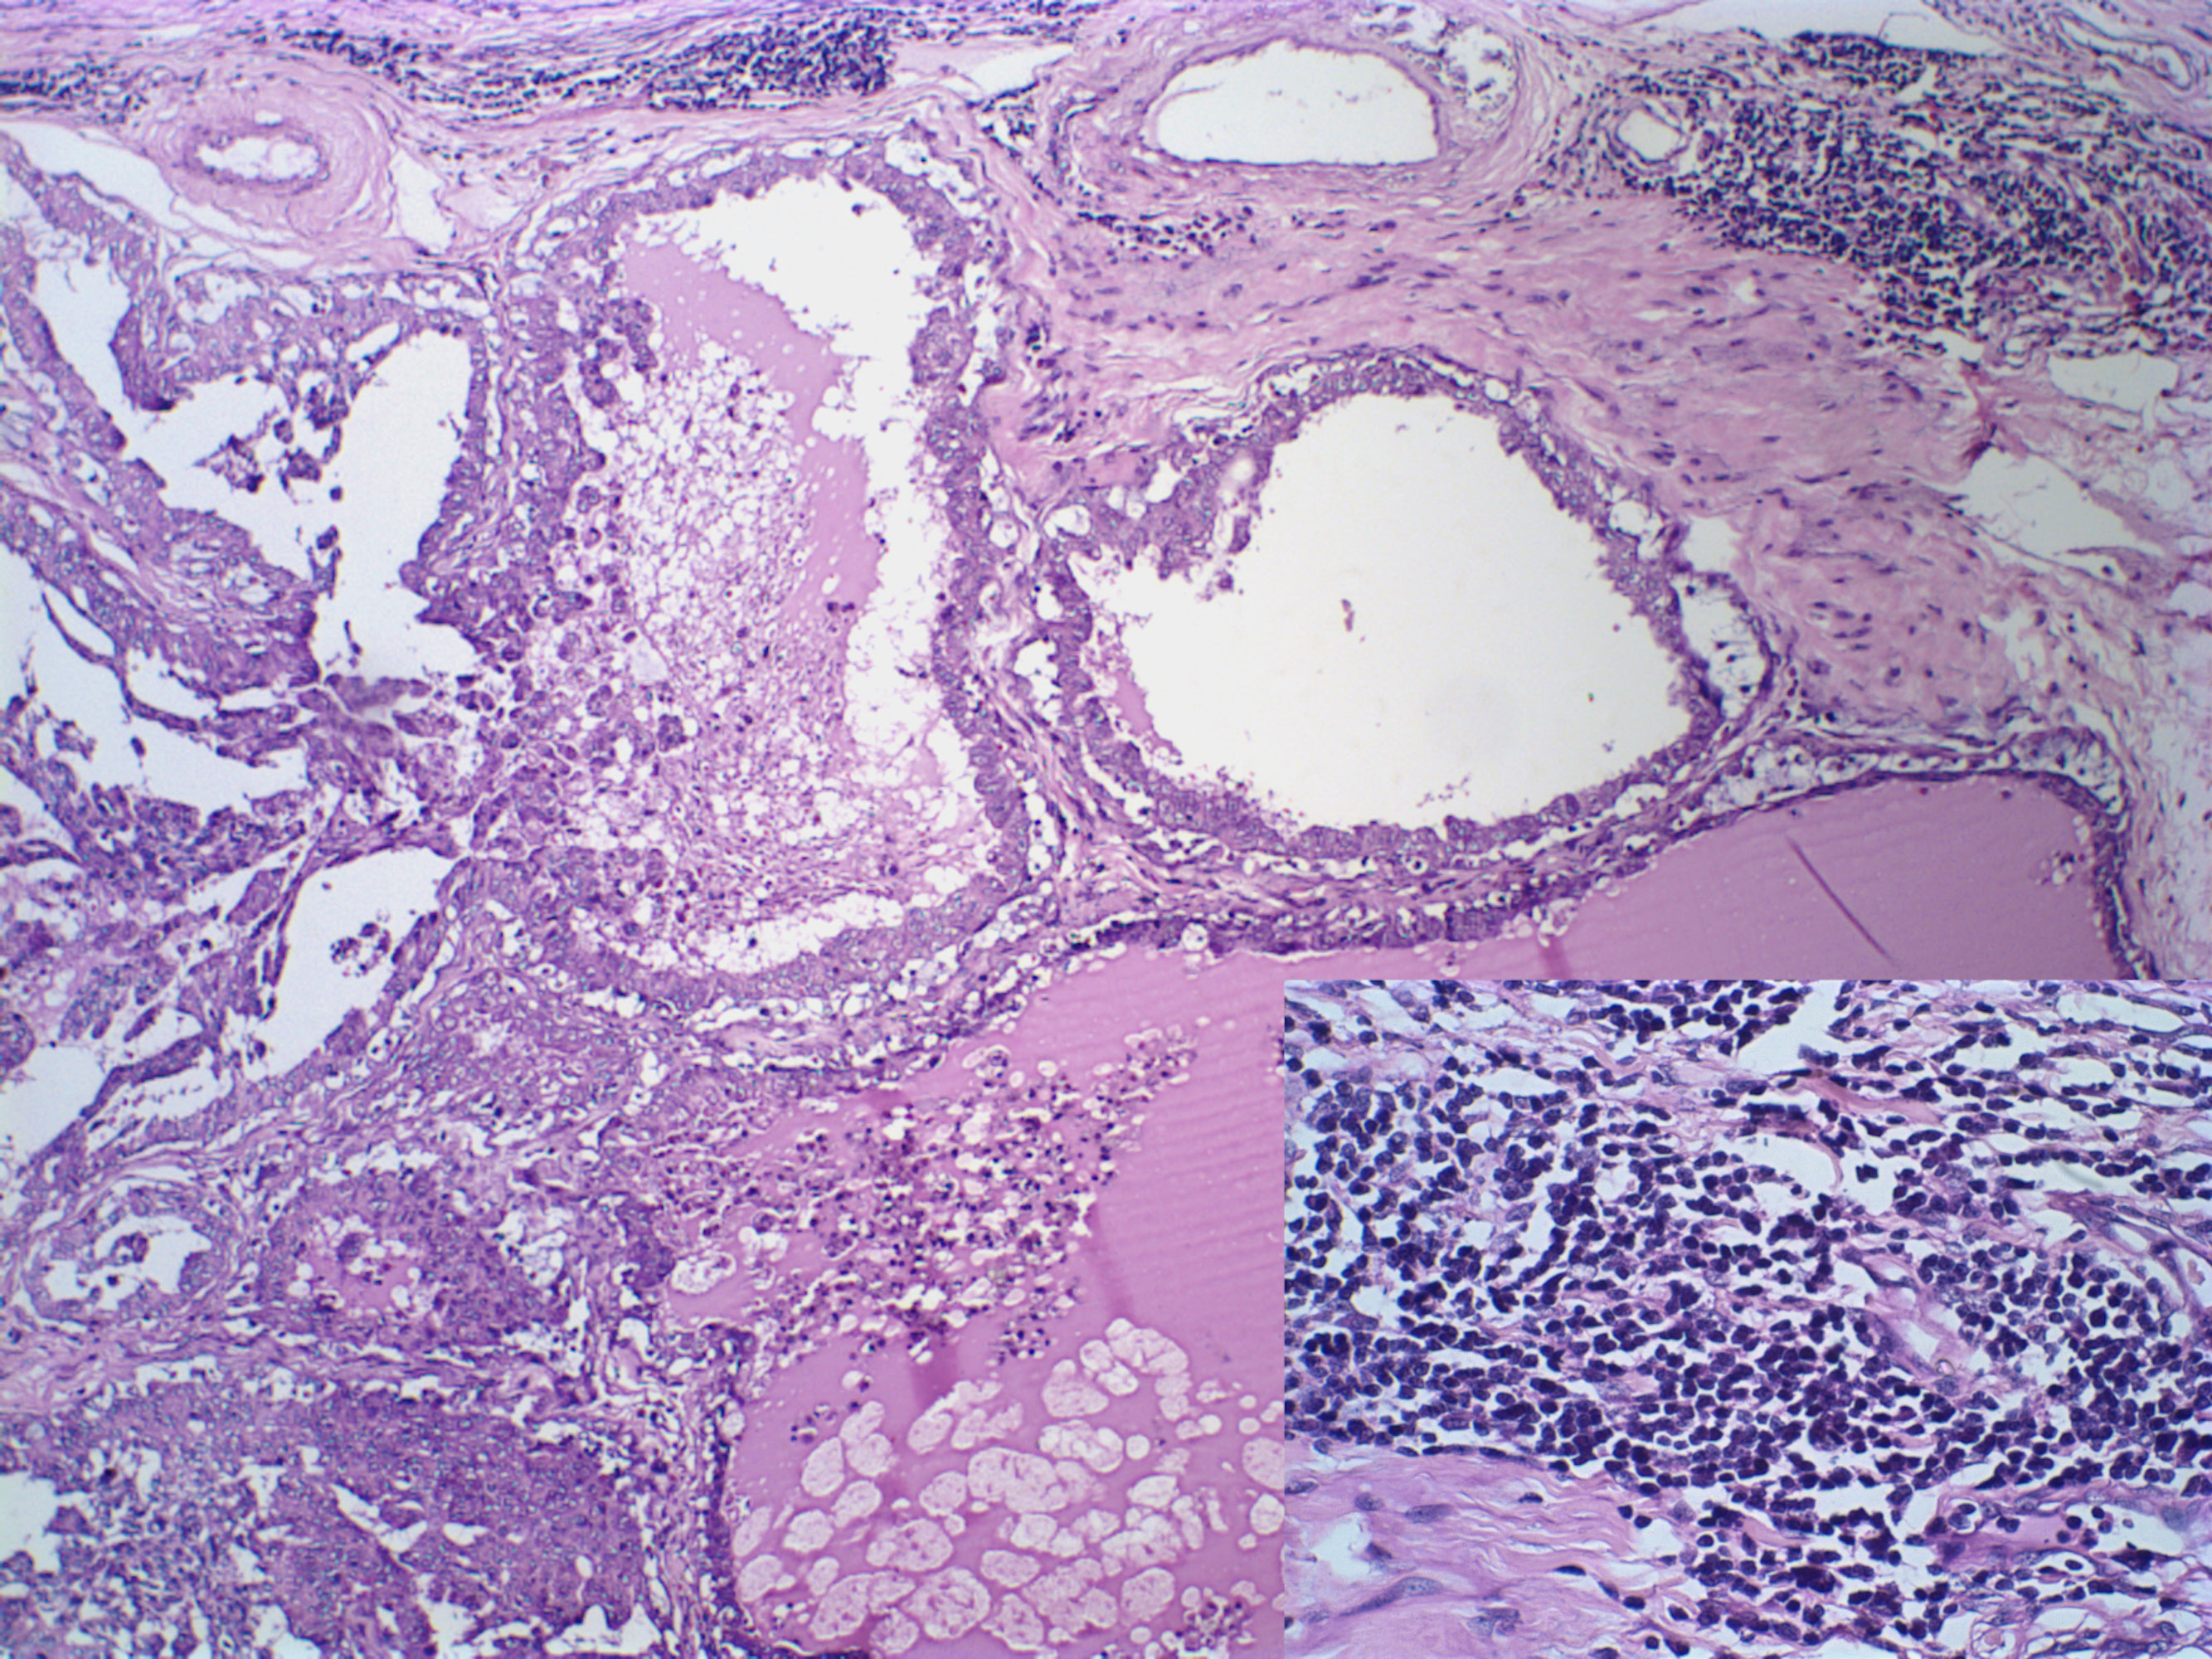

Canine mammary gland carcinosarcoma associated with a multifocal and intense inflammatory infiltrate, presenting an intense lymphocytic component (insert, Hematoxylin and eosin, x1000). Hematoxylin and eosin, x600.